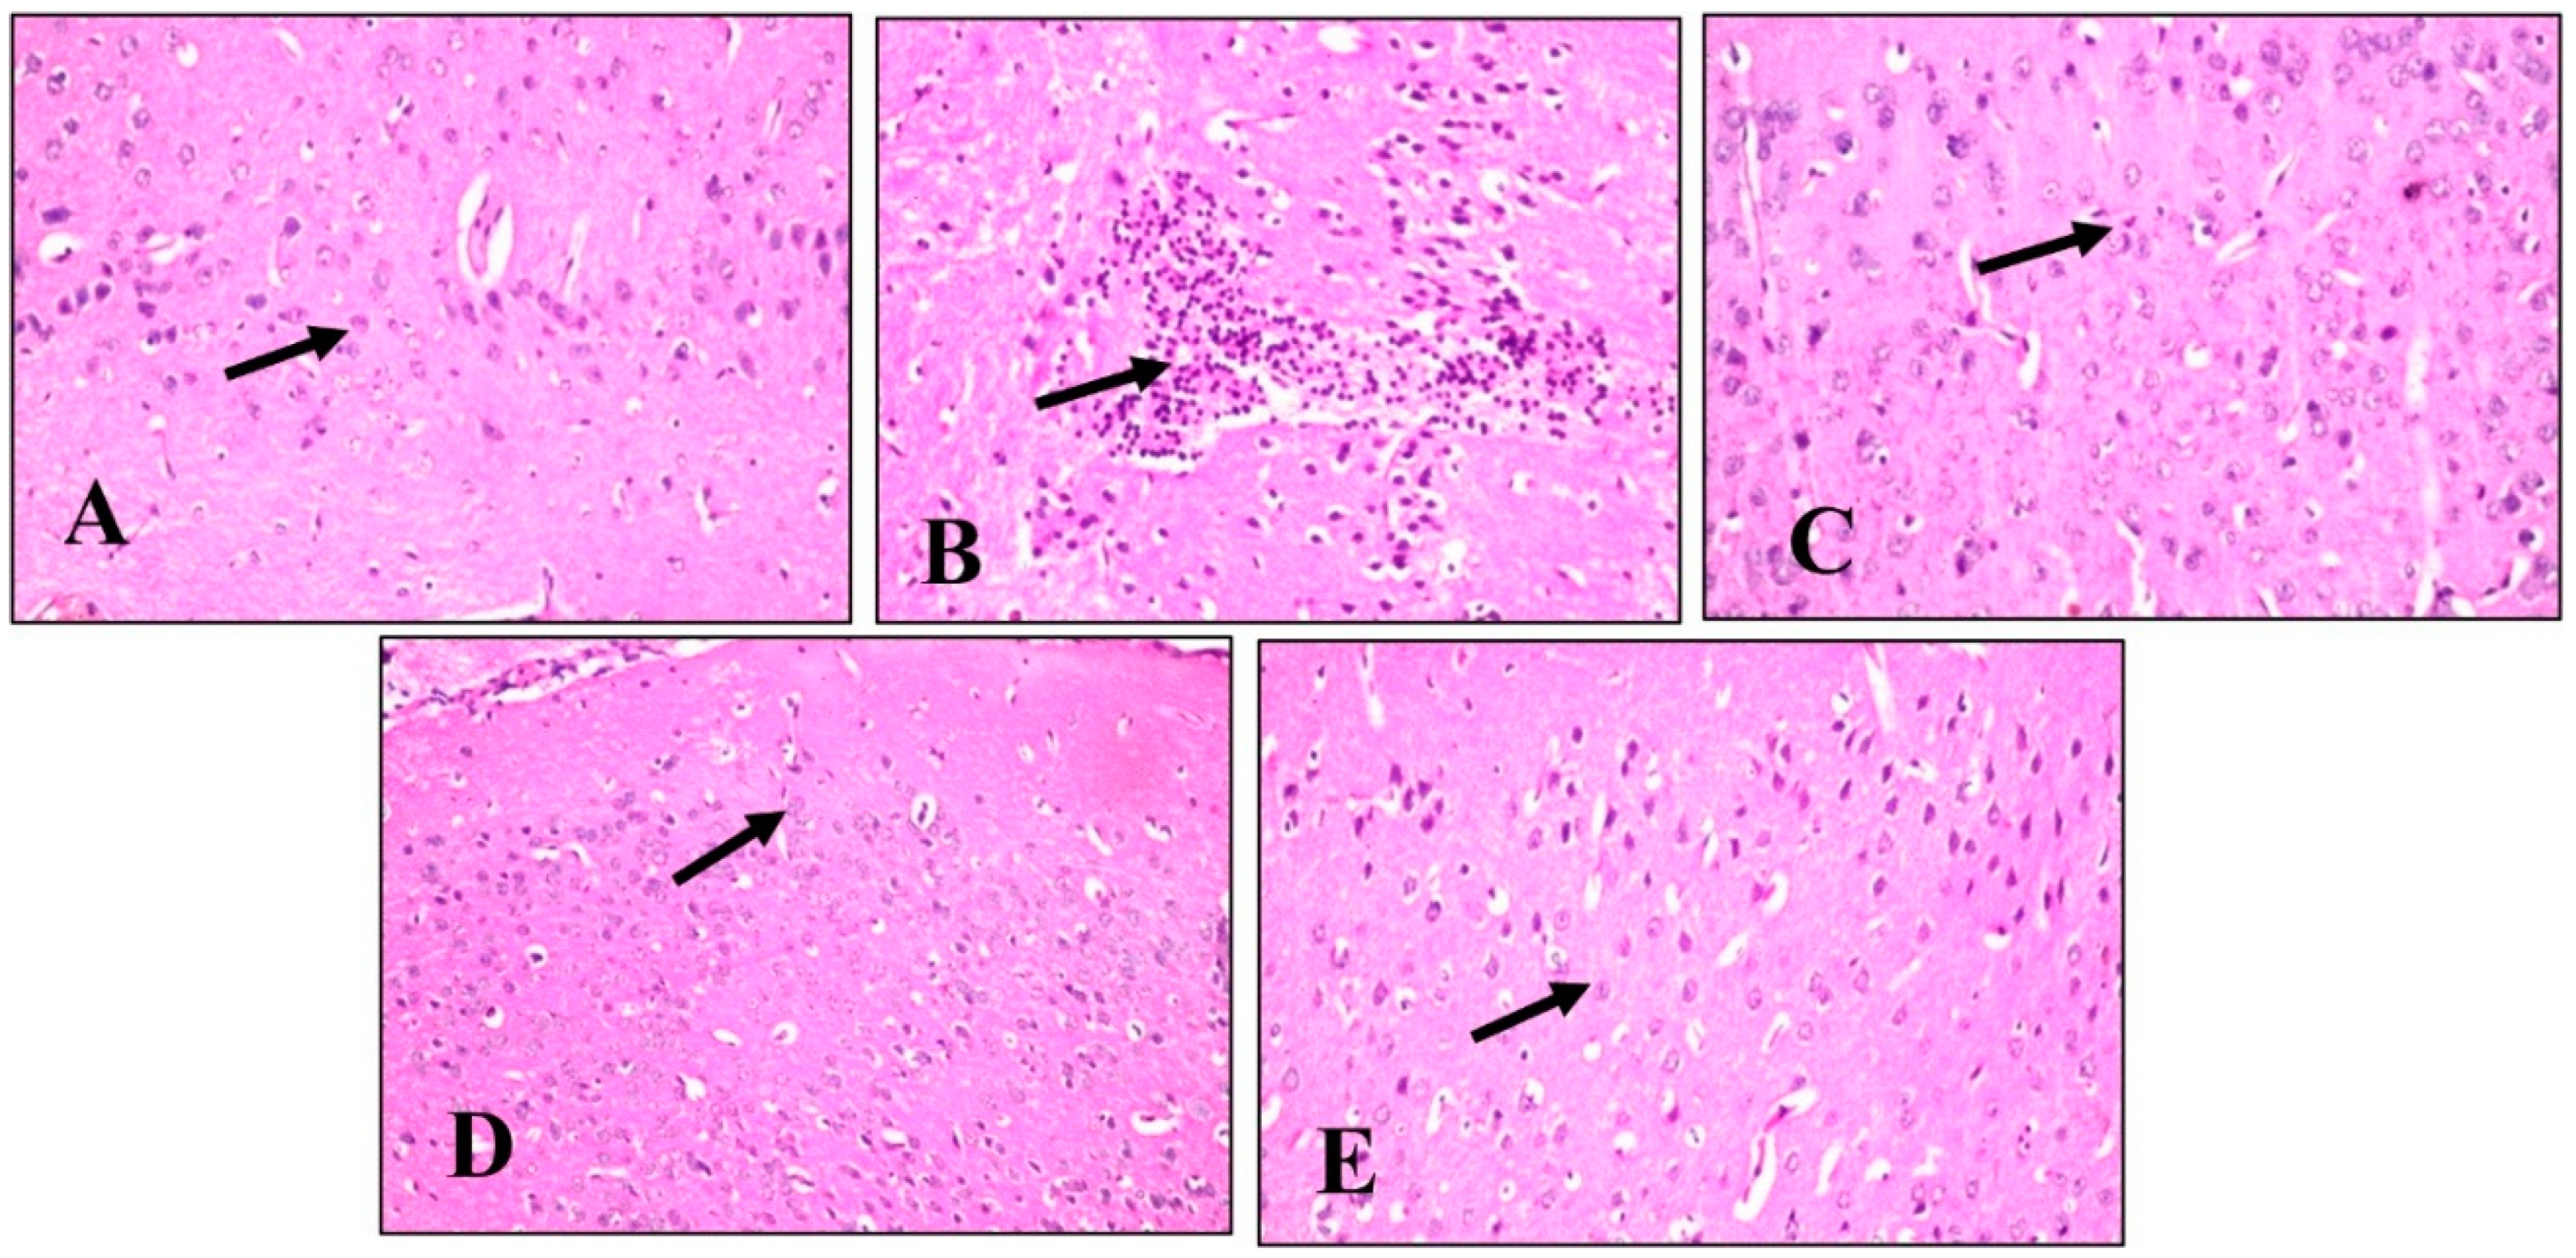

A histopathological examination of different brain tissues was conducted to provide a supplementary explanation of the brain alterations induced by LPS and the effects of BME, BDMF, and BBF administration. Microscopical examination of the cerebral cortex (Figure 6) revealed no histopathological alteration in normal control sections (Figure 6A). While in mice injected with LPS, cerebral cortex sections had nuclear pyknosis and neuronal degeneration with focal gliosis (Figure 6B). Moreover, the cerebral cortex neurons in mice treated with BME, BDMF, and BBF showed normal histological structure (Figure 6C–E, respectively). Additionally, a histopathological examination of the hippocampus subiculum was carried out, as shown in (Figure 7). The results demonstrated that the hippocampus subiculum of normal control mice and animals treated with BME, BDMF, and BBF had no pathological abnormalities (Figure 7A,C–E, respectively). On the contrary, examined hippocampus subiculum sections from mice administered LPS revealed nuclear pyknosis and degeneration in some neurons (Figure 7B).

Microscopical examination of fascia dentata and hilus in the hippocampus (Figure 8) displayed no histopathological alteration in normal control sections, and the normal histological structure of the neurons was recorded in (Figure 8A). Most of the hippocampus fascia dentata and hilus neurons of mice administered with LPS revealed nuclear pyknosis with degeneration (Figure 8B). Regarding examined sections of mice treated with BME, BDMF, and BBF, there was no histopathological alteration when compared to the LPS-administered group (Figure 8C–E, respectively).

Similarly, a microscopical investigation of the brain striatum was conducted in (Figure 9). Striatum sections of normal control mice revealed that the histological structure of neurons was normal and there was no histopathological alteration (Figure 9A). On the other hand, sections from LPS-administered mice showed multiple focal eosinophilic plagues formation (Figure 9B). Surprisingly, fine eosinophilic plagues formation was demonstrated in striatum sections of mice treated with BME (Figure 9C), while examined sections of mice treated with BDMF showed the formation of eosinophilic plagues (Figure 9D). Furthermore, striatum sections of mice treated with BBF revealed focal eosinophilic plagues formation (Figure 9E). Ultimately, microscopical examination of the brain’s cerebellum was exhibited in (Figure 10). The normal histological structure of neurons was observed in cerebellum sections of normal control and all other administered mice groups, with no histopathological alteration, as recorded in (Figure 10A–E, respectively).

According to the above histopathological findings, both BME and BBF fractions effectively ameliorate LPS-induced AD disease in mice, which is consistent with biochemical analysis results.